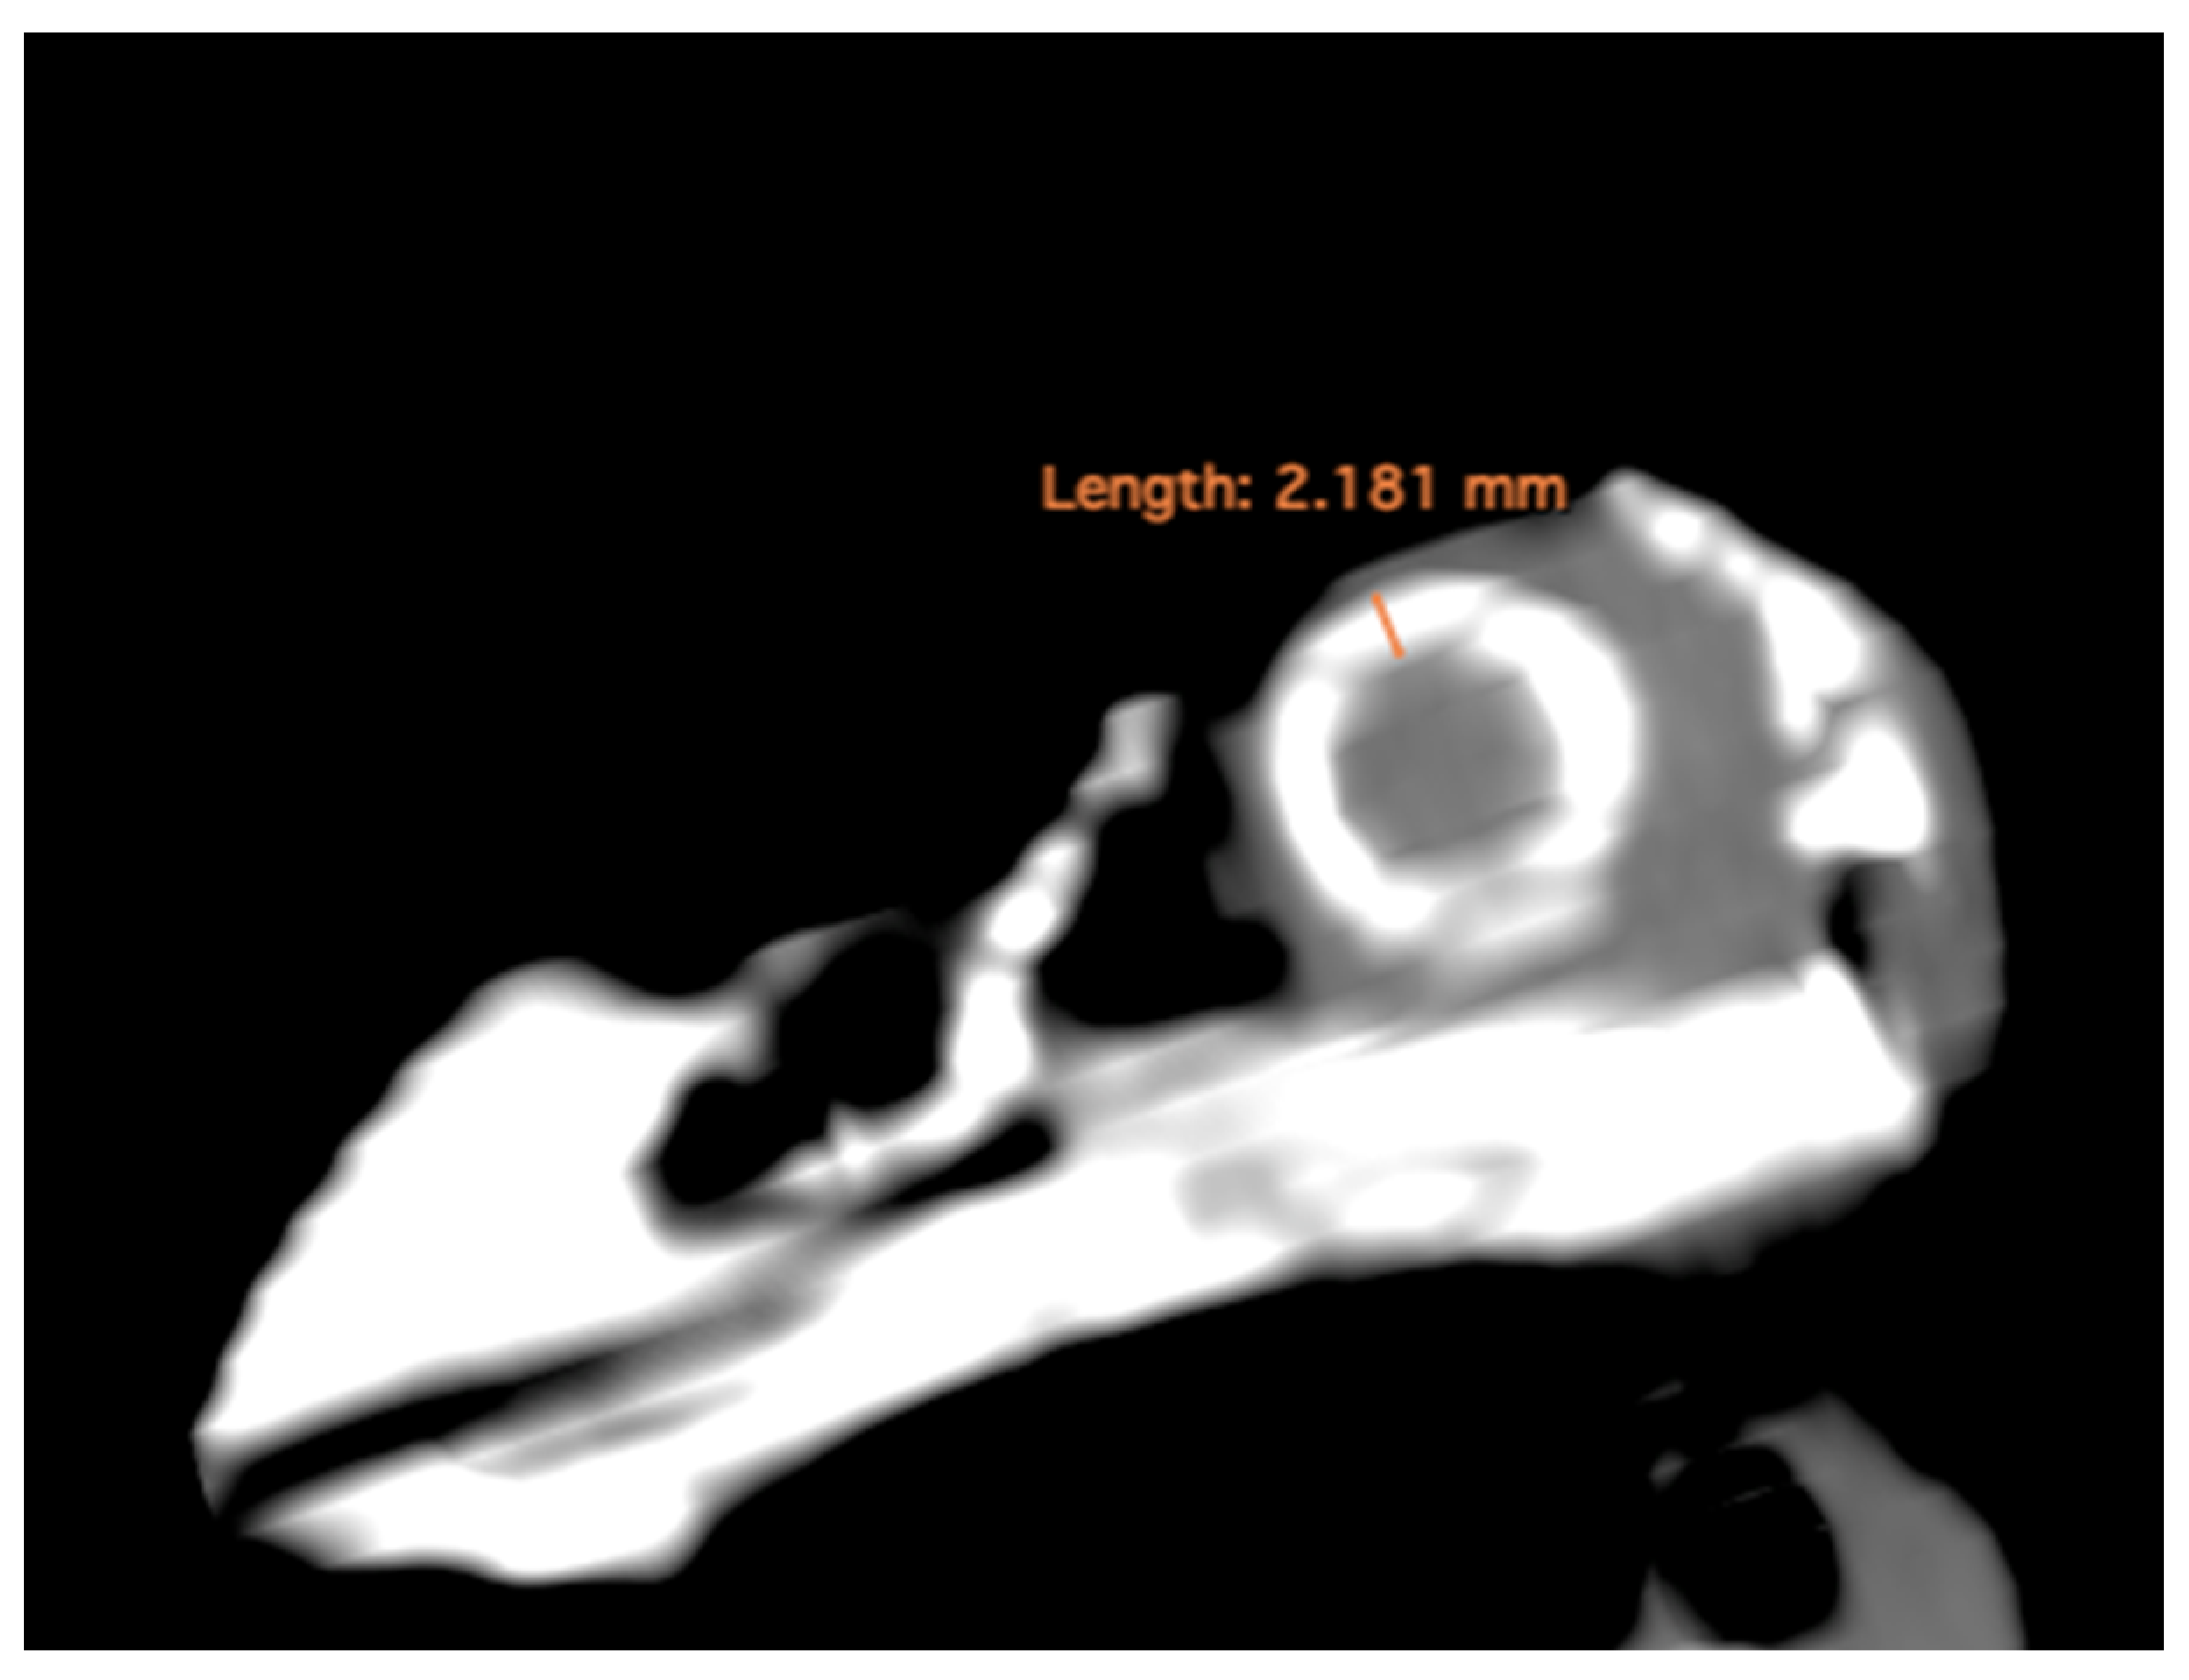

- Lens diameter: This parameter refers to the maximum distance between the lateral and medial edges of the lens, also known as the equatorial diameter (Figure 1A);

- Internal diameter of the sclerotic ring, which represents the maximum distance between the inner lateromedial edges of the ring close to the cornea (Figure 1A);

- External diameter of the sclerotic ring, which corresponds to the maximum distance between the outer lateromedial edges of the ring close to the sclera (Figure 1A);

- Thickness of the sclerotic ring, defined as the distance between the internal diameter of the sclerotic ring and the external diameter, measured in the dorsal arch (Figure 2).